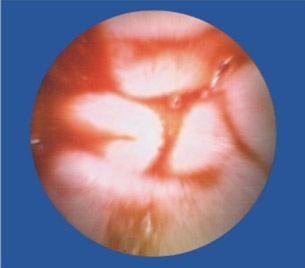

便血,去做检查,痔疮、胃镜、纤维结肠镜都做后,的出结论——小肠流血,但结肠镜够不着,还是看不见在具体位置。因此,也算是体验了下高科技,胶囊内镜。试过后真是感叹,这玩意儿真厉害!比普通药丸子稍大,一喝水下去了。自动掉头,自动拍照,自动传输。拉出来后找护士要了些消毒药水洗了下,细细观察。发现镜头口径有点小最多1mm,确实是高科技,这么小的东西,包括了拍照(可能是2个小时内的连续拍照),无线信号传输,方向姿势控制等等,厉害。

近日,67岁的陈爷爷因为便血导致严重贫血,胃镜、肠镜都做了却查不出病因。被转送到四川肛肠医院后,陈爷爷本来以为要再接受一次痛苦的内镜检查,没想到,医生给出的检查方式却是要他吞下一颗“胶囊”,同时穿上一件连着各种数据线的背心。很快,医生就发现陈爷爷的小肠上面存在一个不断出血的溃疡,经过手术,医生终于治好了陈爷爷的“怪病”。陈爷爷吞下的其实是一种叫“OMOM胶囊内镜”的检查仪器,主要用于小肠疾病的排查。